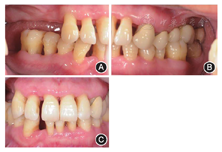

根分叉病变(furcation involvement,FI)3度,电活力测58,对照牙56。全口根尖X线片见图1,牙周检查表见图2。全口牙列不齐,上下前牙散在间隙,

间隙2 mm,

间隙3 mm。前牙Ⅱ度深覆

,Ⅰ度深覆盖,上颌中线左偏2 mm(图3),上下颌骨位置正常,面部对称。关节检查未见明显异常。